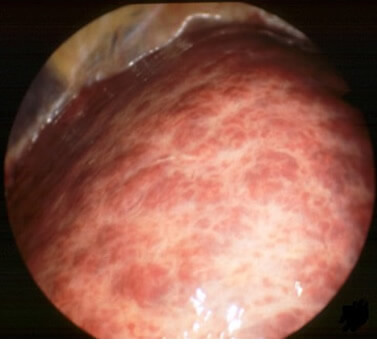

C型慢性肝炎とはC型肝炎ウイルスの感染が原因でおこる疾患です。C型肝炎ウイルスの感染からおおむね30年程度で徐々に慢性肝炎から肝硬変へと進行していきます。下の写真はおなかの中にいれたカメラ(腹腔鏡)で肝硬変に進行していく様子を見たものです。肝硬変になると表面がでこぼこになる様子が分かります。肝硬変になっても よほど進行しないと自覚症状はでませんが、年間約8%の確率で肝臓がんが発生しますので十分な注意が必要です。